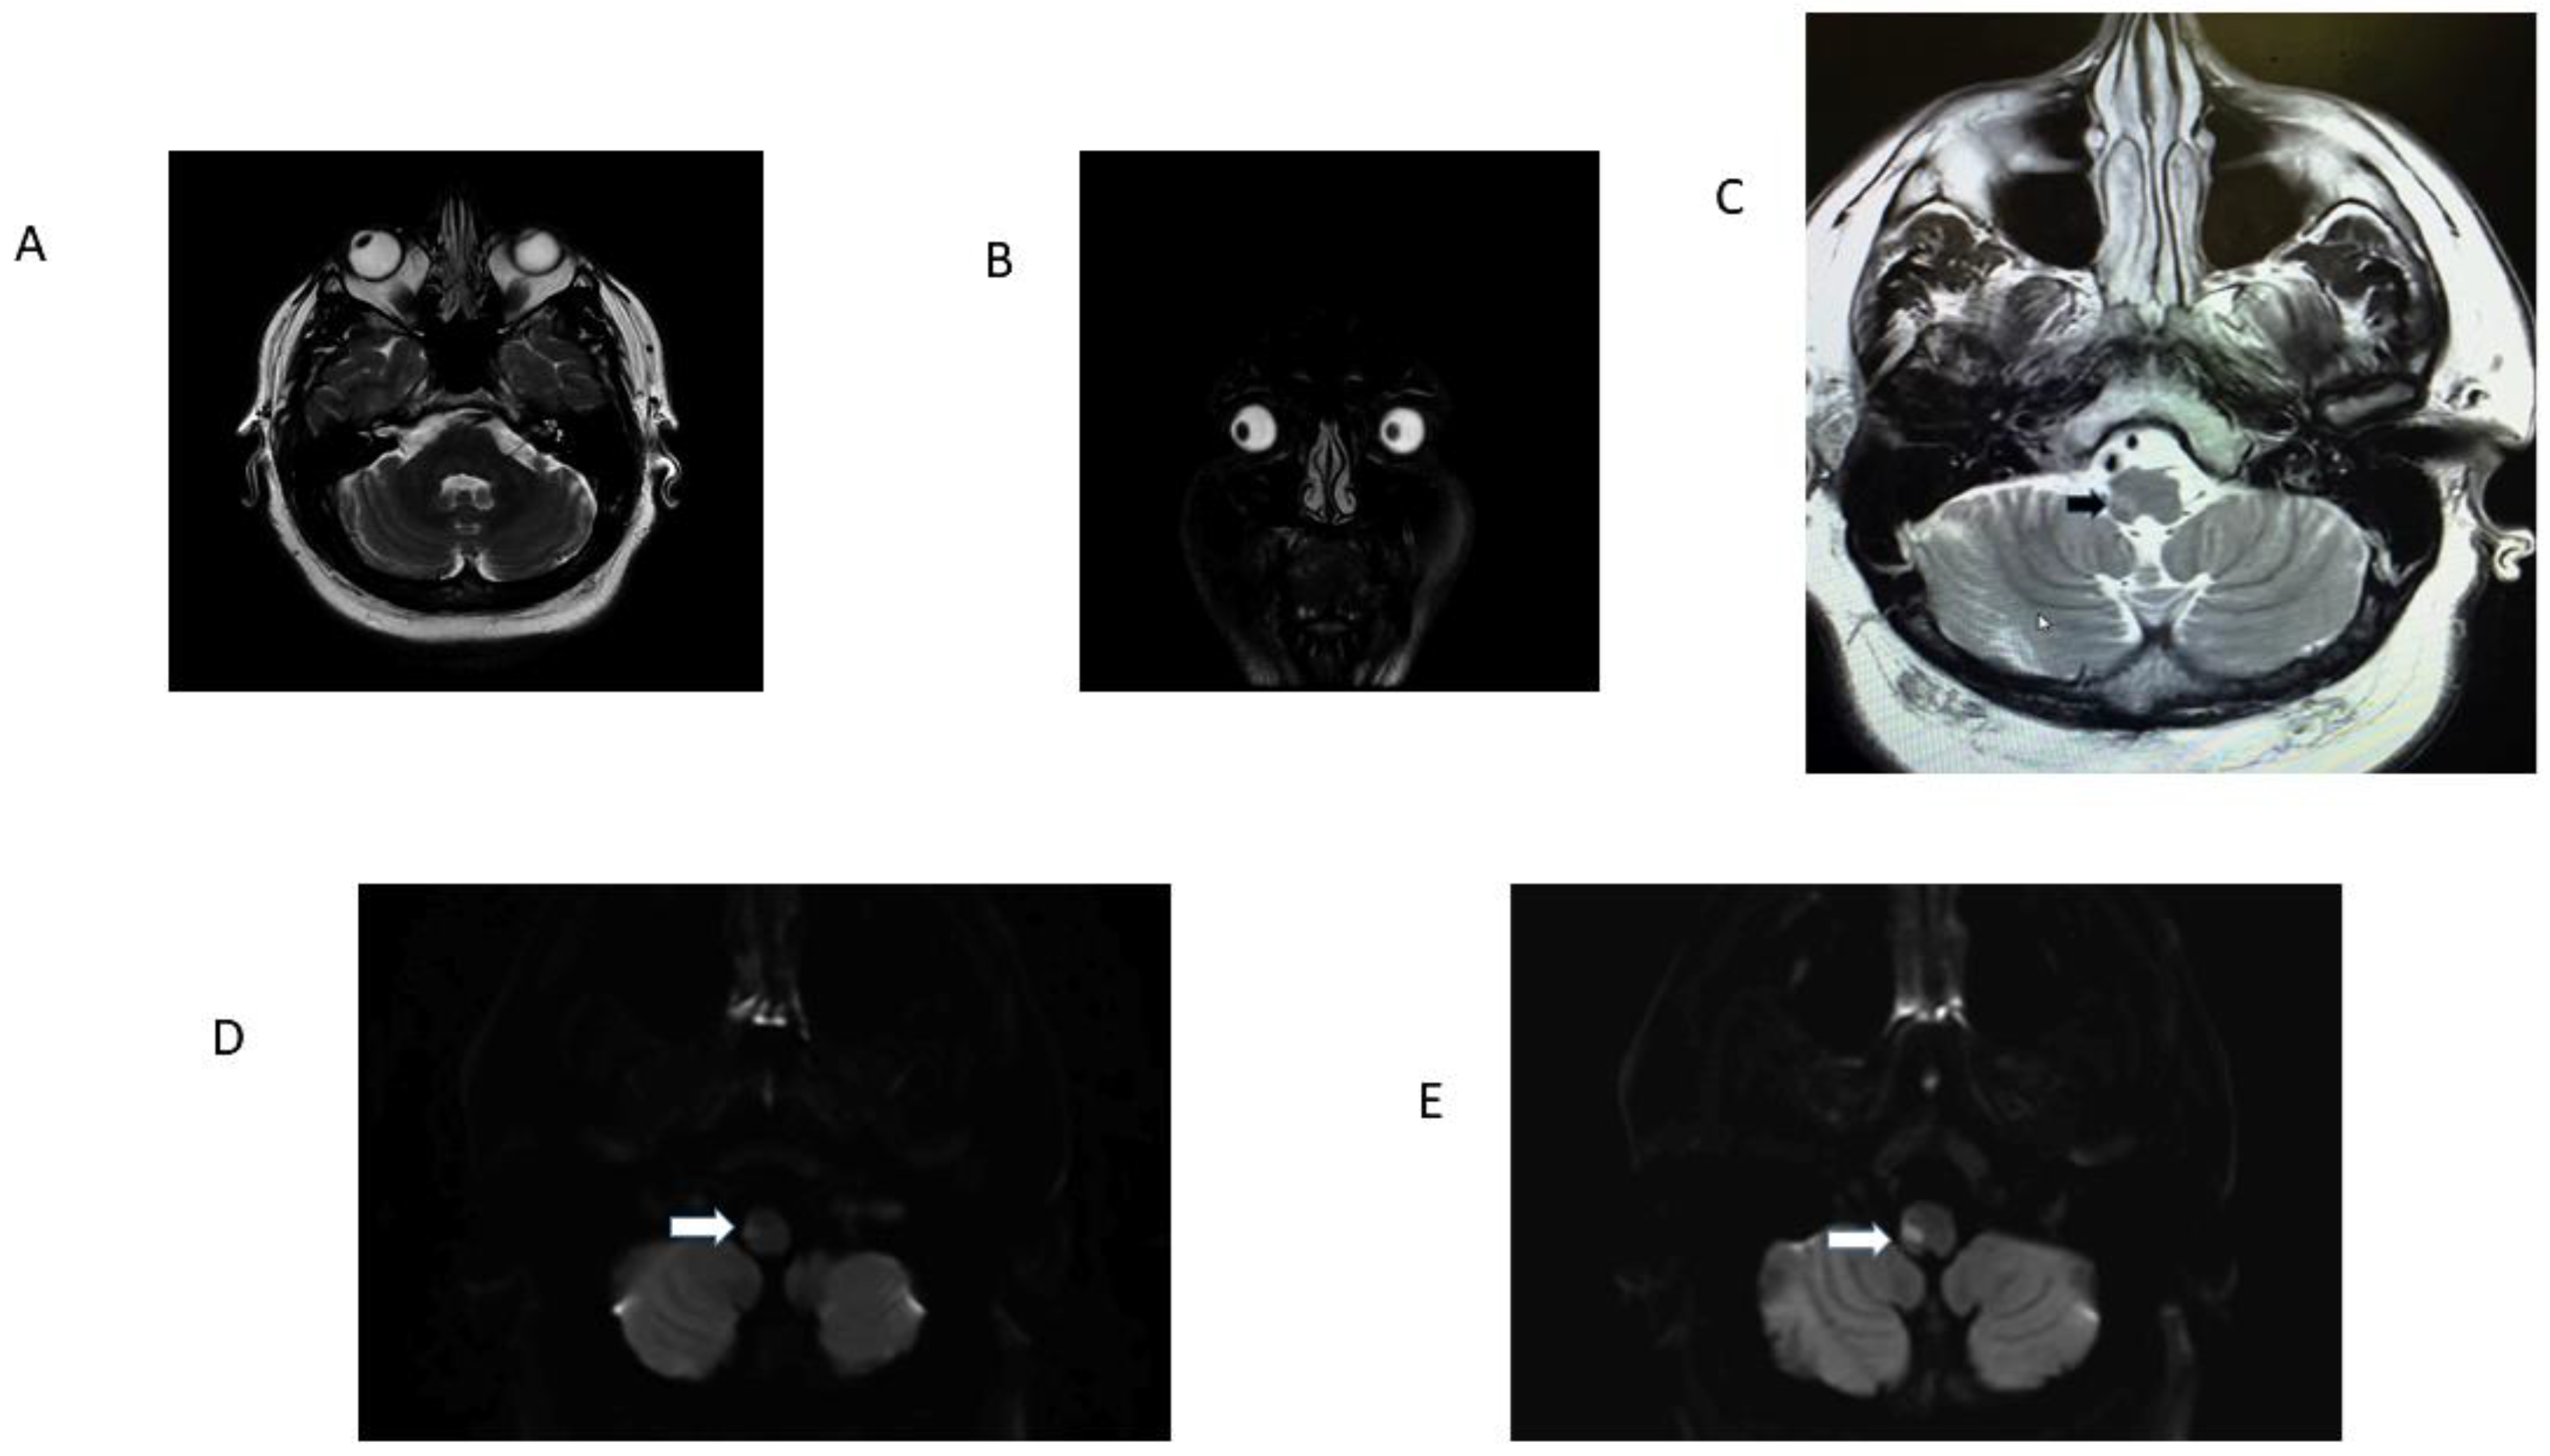

Figure 3.

Patient 13 Table 1. Panel (A): note radiographic conjugate right ocular deviation, it correlated with clinical right OLD; panel (B) is a coronal T2-weighed MRI. Observe radiographic rightward deviation of the eyes in the coronal plane. Panel (C) is a T2 FLAIR image that identifies the precise location of the ischemic stroke (black arrow). Panels (D) and (E) are adjacent axial DWI scans. Note infarcts involving the right LVST and ICP responsible for OLD (white arrows). The ADC map confirmed diffusion restriction.